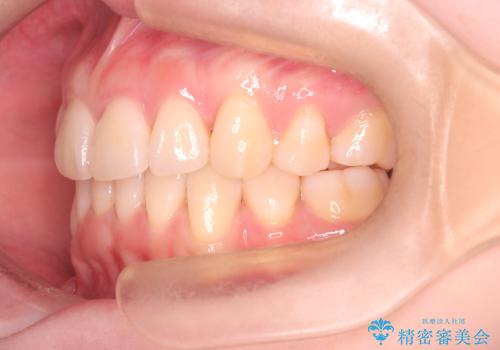

- 前歯が出ていることと、下の歯のがたがたで歯磨きがしにくいことを主訴に来院されました。

マウスピース矯正の希望があり、ワイヤーリカバリの可能性を伝えたうえでインビザライン抜歯矯正を行っています。

来院が途中途絶えたこともあり、4年ぐらい期間がかかりましたが、インビザラインだけで治療を終えることができました。